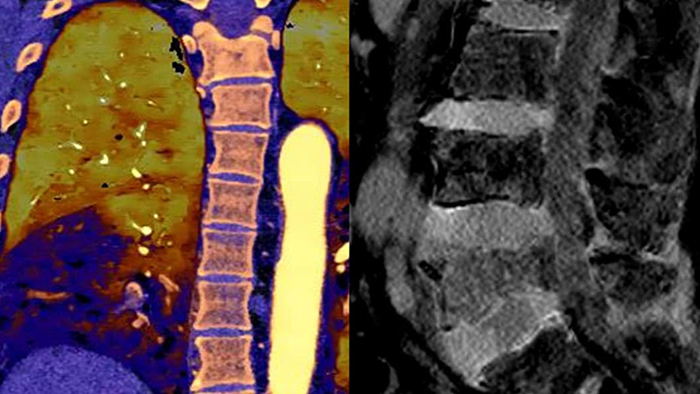

Nuestro CT con detección espectral de Philips, nos permite adquirir datos convencionales y espectrales en una sola exploración, sin cambios en nuestro flujo de trabajo actual.

Observe las diferencias entre un detector espectral CT y un CT Convencional

Aprenda sobre las ventajas del detector espectral CT